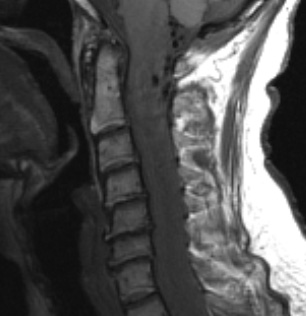

1A2,3 A T1-weighted image without (1A2) and with contrast (1A3) shows marked tumor enhancement.